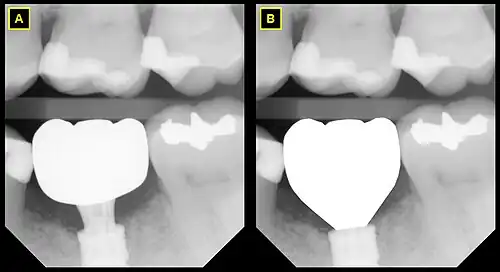

B This emergence profile respects the gingival architecture and emerges fully subgingivally.

In implant dentistry, running room refers to the apico-coronal distance between the platform of a dental implant and the gingival margin. It is a critical factor in restorative implant dentistry because it is effectively the "vertical distance [available subgingivaly] to make a transition from the smaller diameter prosthetic platform of an implant to the larger cross-sectional cervical shape of the tooth being restored."[1] The term was coined by Jonathan Zamzok, a Manhattan prosthodontist, in the late 1990s.[2]

Adequate running room is necessary to allow the implant-supported crown to exhibit a tooth-shaped contour despite the smaller diameter and circular nature of implant platforms.[3] For example, the mean mesial-distal dimension of a maxillary central incisor at the points at which it contacts the adjacent teeth is 8.6 mm, and the mean mesial-distal dimension of the same tooth at the cementoenamel junction (CEJ) is 6.4 mm.[4] Even though the implant diameter chosen for the maxillary central incisor is usually around 4–5 mm, the supragingival tooth contours need to mimic those of the natural tooth if esthetic success is intended.

As the anatomical crown and root tapers towards the apex, the mesial-distal dimension decreases, and so the mean mesial-distal dimension at the marginal crest of bone, which lies approximately 2 mm apical to the CEJ, is smaller. The tooth has the apico-coronal distance from the marginal crest of bone to the contact point in order to increase from the much narrower mesial-distal dimension to the greater mesial-distal dimension, and this distance is subgingival (below the gum line). Running room refers to this subgingival apico-coronal distance.

In general, it is recommended that implants be given approximately 3mm of running room in compliance with the rule of thumb that implants should be placed as deep as necessary and as shallow as possible.[5]